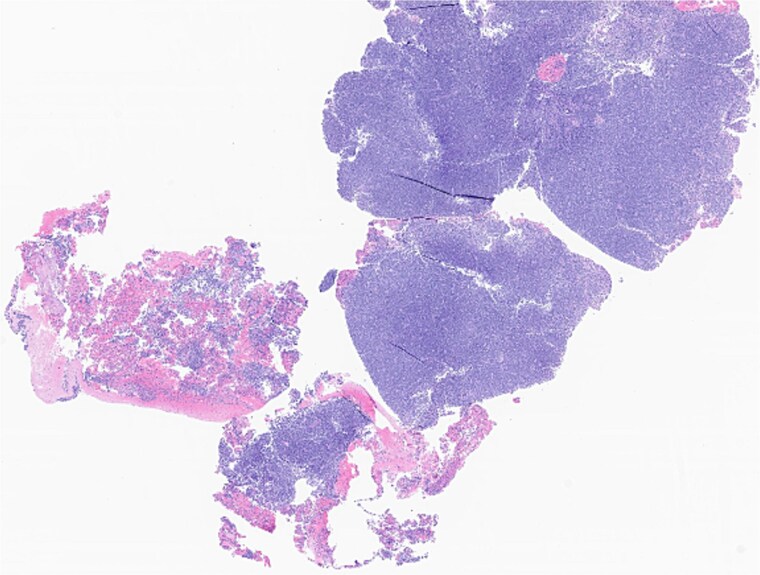

腮腺的同步鳞状细胞癌(SCC)和慢性淋巴细胞白血病(CLL)是罕见的,个性化治疗的证据有限。我们报告一位75岁男性既往皮肤鳞状细胞癌,表现为高代谢腮腺肿块和颈部淋巴结病;细针穿刺证实SCC。手术显示多发淋巴结低分化SCC和CLL。他接受了放疗,但出现了局部SCC复发,没有全身CLL症状。耳部复发需要广泛的手术切除和重建。遗传谱显示高肿瘤突变负担(bbb50突变/Mb)和ARID1B、CDKN2A、MSH2、PMS2和TP53突变。他接受了6个周期的西妥昔单抗治疗,随后是基于循环DNA水平上升的西妥昔单抗靶向治疗。本病例强调了遗传谱和TMB、FISH和免疫组织化学等工具在管理晚期或复杂腮腺恶性肿瘤(包括同步SCC和CLL)的风险分层和个性化治疗中的价值,以优化患者的预后。

Synchronous squamous cell carcinoma (SCC) and chronic lymphocytic leukemia (CLL) in the parotid gland is rare, with limited evidence on personalized treatment. We report a 75-year-old male with prior cutaneous SCC who presented with a hypermetabolic parotid mass and cervical lymphadenopathy; fine needle aspiration confirmed SCC. Surgery revealed poorly differentiated SCC and CLL in multiple lymph nodes. He underwent radiotherapy but developed regional SCC relapse without systemic CLL symptoms. Recurrence in the ear required extensive surgical resection and reconstruction. Genetic profiling showed high tumor mutational burden (>50 mutations/Mb) and mutations in ARID1B, CDKN2A, MSH2, PMS2, and TP53. He received six cycles of cemiplimab followed by cetuximab-based targeted therapy, based on rising circulating DNA levels. This case emphasizes the value of genetic profiling and tools like TMB, FISH, and immunohistochemistry for risk stratification and personalized treatment in managing advanced or complex parotid malignancies, including synchronous SCC and CLL, to optimize patient outcomes.